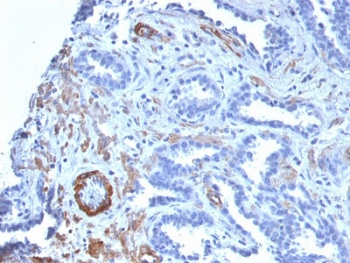

IHC: Formalin-fixed, paraffin-embedded human breast carcinoma stained with SMMHC antibody (MYH11/923).